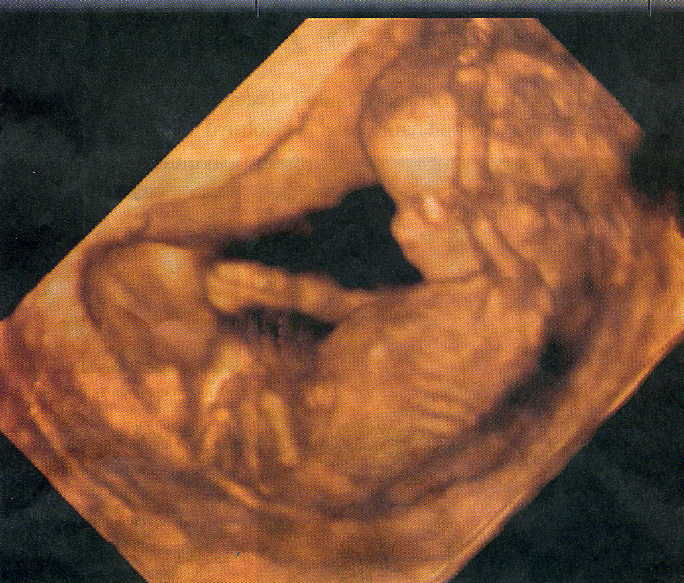

12weeks3monthsFront PrebirthStory PRECIOUS UNBORN IN WOMB PICS